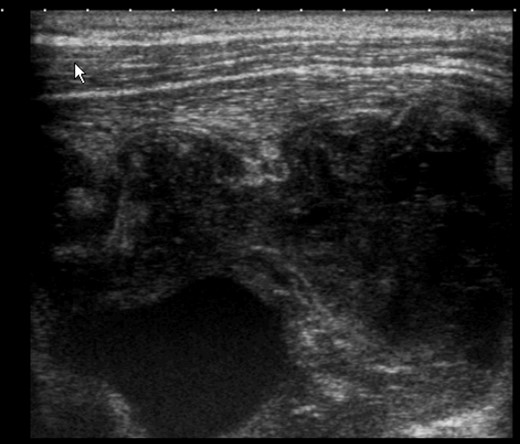

The patient underwent adjuvant therapy with four cycles of doxorubicin and cyclophosphamide. Six months after surgery, the patient showed a hard and painful nodule adjacent to the suture and adherent to the chest wall. Ultrasound confirmed a heterogeneous multicystic nodule of 9 × 7 cm (Fig. 5). Chest CT revealed right pleural effusion, pleural thickening and consolidation of the adjacent parenchyma. Cytological analysis raised a suspicion for the presence of malignant cells. Pleural biopsy was negative for malignancy.

Ultrasound of the mastectomy bed showing a hypoechoic solid mass in subpectoral topography with signs of muscle invasion.